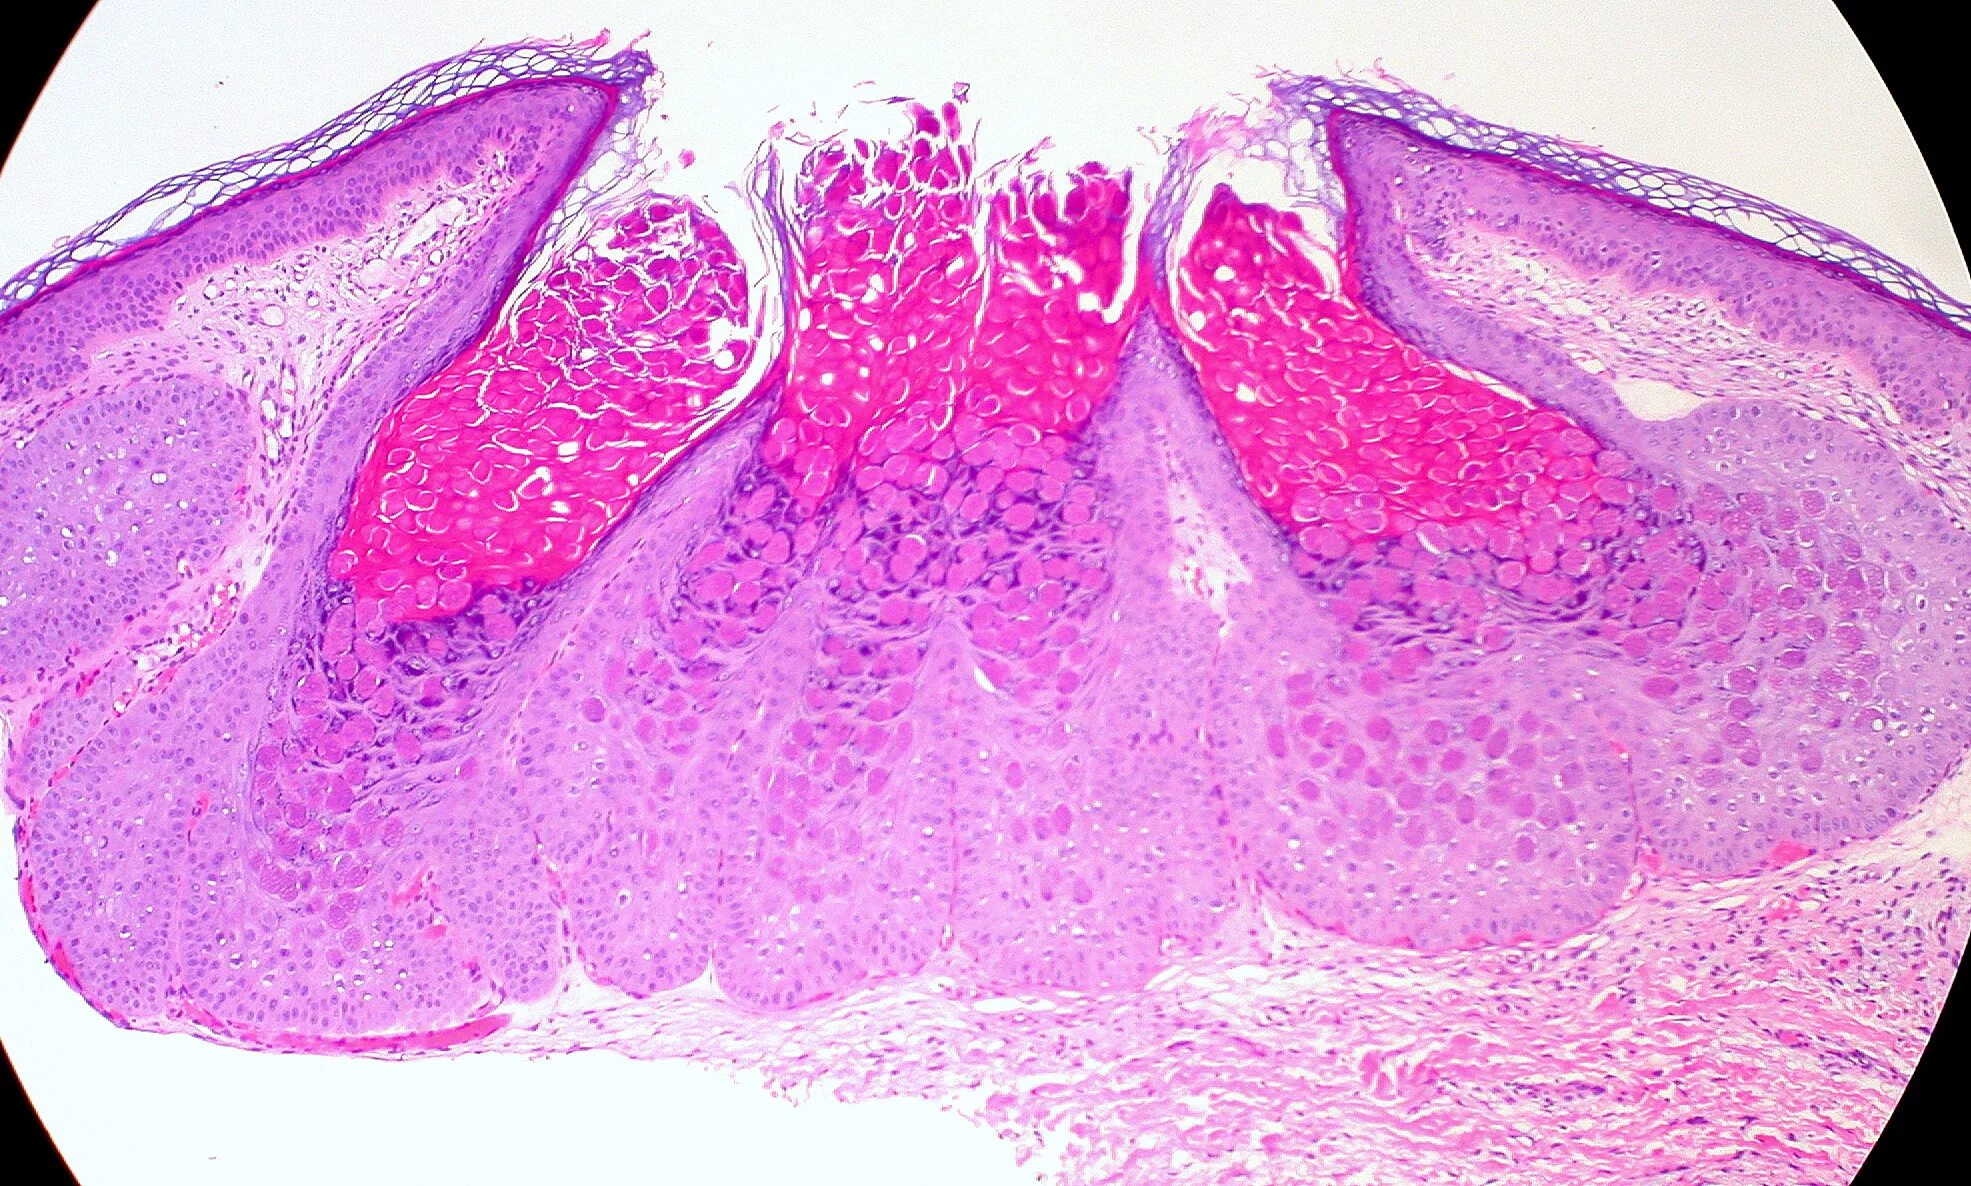

Папиллома гистология